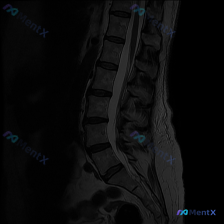

整理到一份腰椎MRI T2序列矢状位的影像学分析资料,先放影像上的客观发现,大家先从读片角度聊聊: 主要影像表现 1. 椎间盘:L2/3、L3/4、L4/5、L5/S1 T2信号明显减低(“黑盘”),伴椎间隙不同程度变窄;L4/5、L5/S1可见椎间盘向后突出,压迫硬膜囊前缘,L4/5更明显。 2....